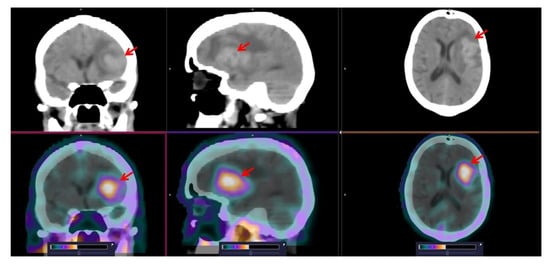

3.3. [99mTc]Tc-TG SPECT/CT Imaging of Nodal and Extranodal Lesions

4. Discussion